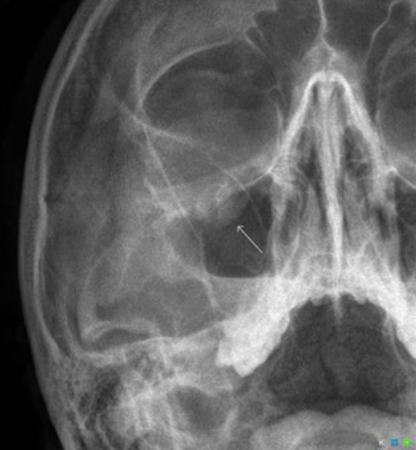

Blowout/tripod fracture

What is a blowout/tripod fracture?

Direct blow to the orbit and maxilla or zygoma causing fractures to orbital floor and lateral orbital margin